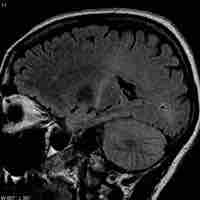

Injuries, Diseases, and Disorders of the Central Nervous System

Traumatic Brain Injury

Traumatic brain injury (TBI) occurs when an external force injures the brain and can be caused by a direct impact or by acceleration alone.

Cerebrovascular Accident

A cerebrovascular accident results from loss of oxygenated blood to a region of the brain and is typically accompanied by neuronal loss.

Transient Ischemic Attacks

A transient ischemic attack is similar to a stroke; though without permanent damage, it can serve as an important risk factor for stroke.

Alzheimer's Disease

Alzheimer's disease is an age-linked neurodegenerative disorder characterized by marked dementia.

Brain Tumors

A brain tumor is a pathological abnormal growth of cells in the brain.

Amyotrophic Lateral Sclerosis

Amyotrophic lateral sclerosis (ALS) is caused by degeneration of upper and lower motor neurons, resulting in muscle weakness and atrophy.